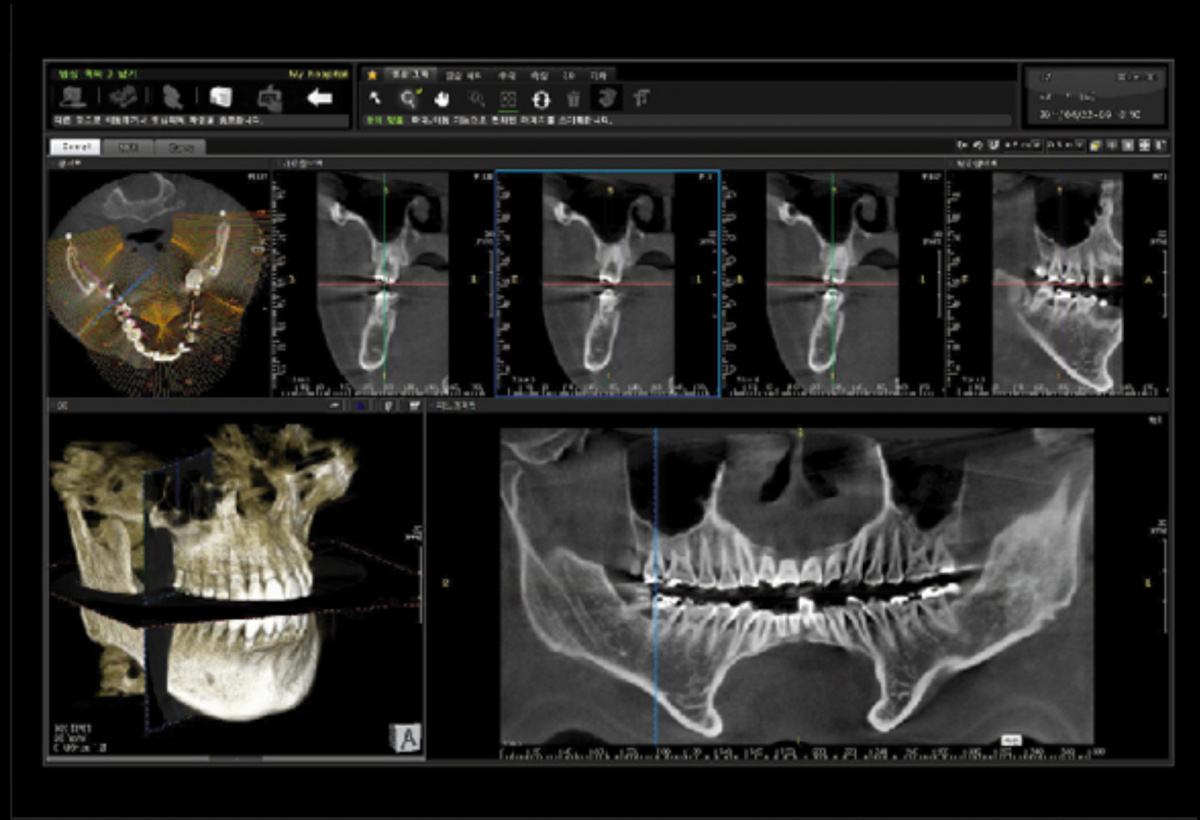

Немаловажным, а может главным вопросом, является универсальность программы-просмотровщика, в которой будут работать врачи-стоматологи. У Papaya 3D есть два варианта программ: Triana и OnDemand3D. Оба просмотровщика обладают схожим интерфейсом и имеют самые важные опции, а именно:

• режим MPR (многоплоскостная реконструкция). Именно здесь выстраивается интересующий участок челюсти или зуба для анализа.

• панорамный реформат. Возможность постройки классической и сегментарной панорамы позволяет продемонстрировать план лечения пациенту, а также оценить расположение анатомических структур на боковых кросс-секциях.

• модуль дентальной имплантации. Возможность виртуальной установки дентального имплантата с анализом окружающей костной ткани. В библиотеке представлен широкий спектр имплантологических систем с индивидуальной прорисовкой имплантата.

• выделение нижнечелюстного канала позволяет продемонстрировать расположение важного анатомического образования и определить зону безопасности при проведении лечения.

• функции плотности, линейных измерений и угла – необходимы для получения полноценной информации для последующего лечения.

• 3D режим – показывает трехмерную модель челюсти с целью определения аномалий, деформация, а также визуализации виртуальных имплантатов.

triana3.jpg triana4.jpg triana5.jpg

OnDemand3D (1).jpg OnDemand3D (2).jpg OnDemand3D 1.jpg

Таким образом обе программы являются простыми в пользовании, но обладающими обширным спектром возможностей для диагностики любыми специалистами-стоматологами. В данные программы происходит загрузка классических файлов DICOM 3.0, которые являются общепринятым форматом записи данных пациента. Это важный момент, так как позволяют врачу, имеющему полную версию программы загружать даже сторонние исследования и просматривать их в этих программах. Простота в освоении этих программ позволяет даже специалисту, не работающему раннее с этими программами, быстро адаптироваться и получить качественную информацию. Возможность выгрузки STL-файла дополнительно создает возможность интегрировать данные с цифровым ортопедическим протоколом.